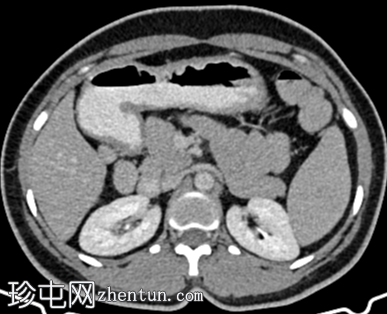

轴位增强扫描

动脉期

脾脏内可见一圆形低密度病灶,动脉期呈周边环状强化,延迟期呈轻微向心性充盈

未见钙化、动静脉畸形或动脉瘤

学特征为:病灶周围呈放射状强化,中心呈放射状强化,周围环状强化,中心充盈轻微。增强扫描后可见中央星状瘢痕。